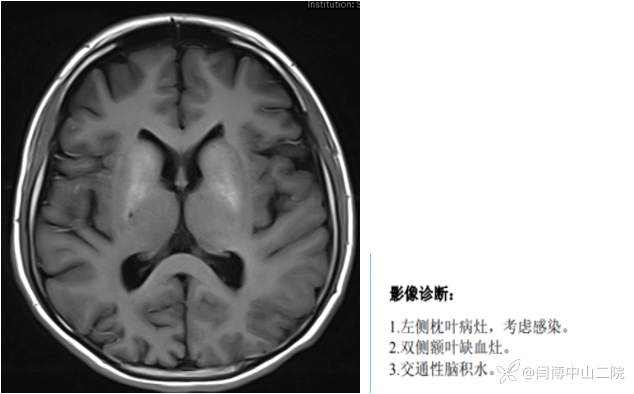

我曾遇到一个病例:16岁男性青少年,头痛,幻觉,发热伴有癫痫发作,MRI显示颅内多发性病变,外院按照病毒性脑炎治疗,效果差。转到我院进行治疗,当天就做了头部MRI如下,请大家考虑一下患者的诊断。

我当时就下了诊断,因为我看到了患者的双侧基底节区病变——钙化,加上左侧枕叶肿胀。直接秒杀:MELAS,后期的进一步检查证实了我的诊断。《中国线粒体疾病指南》中,明确提出线粒体病的影像学特点之一:CT出现双侧基底节区钙化。只不过《指南》给出的是CT片子,需要头脑转换一下:在MRI片子上,双侧基底节区钙化应该是什么样子?思维跨过了这一关,结论就出来了。下图是患者后期补做的CT图片。